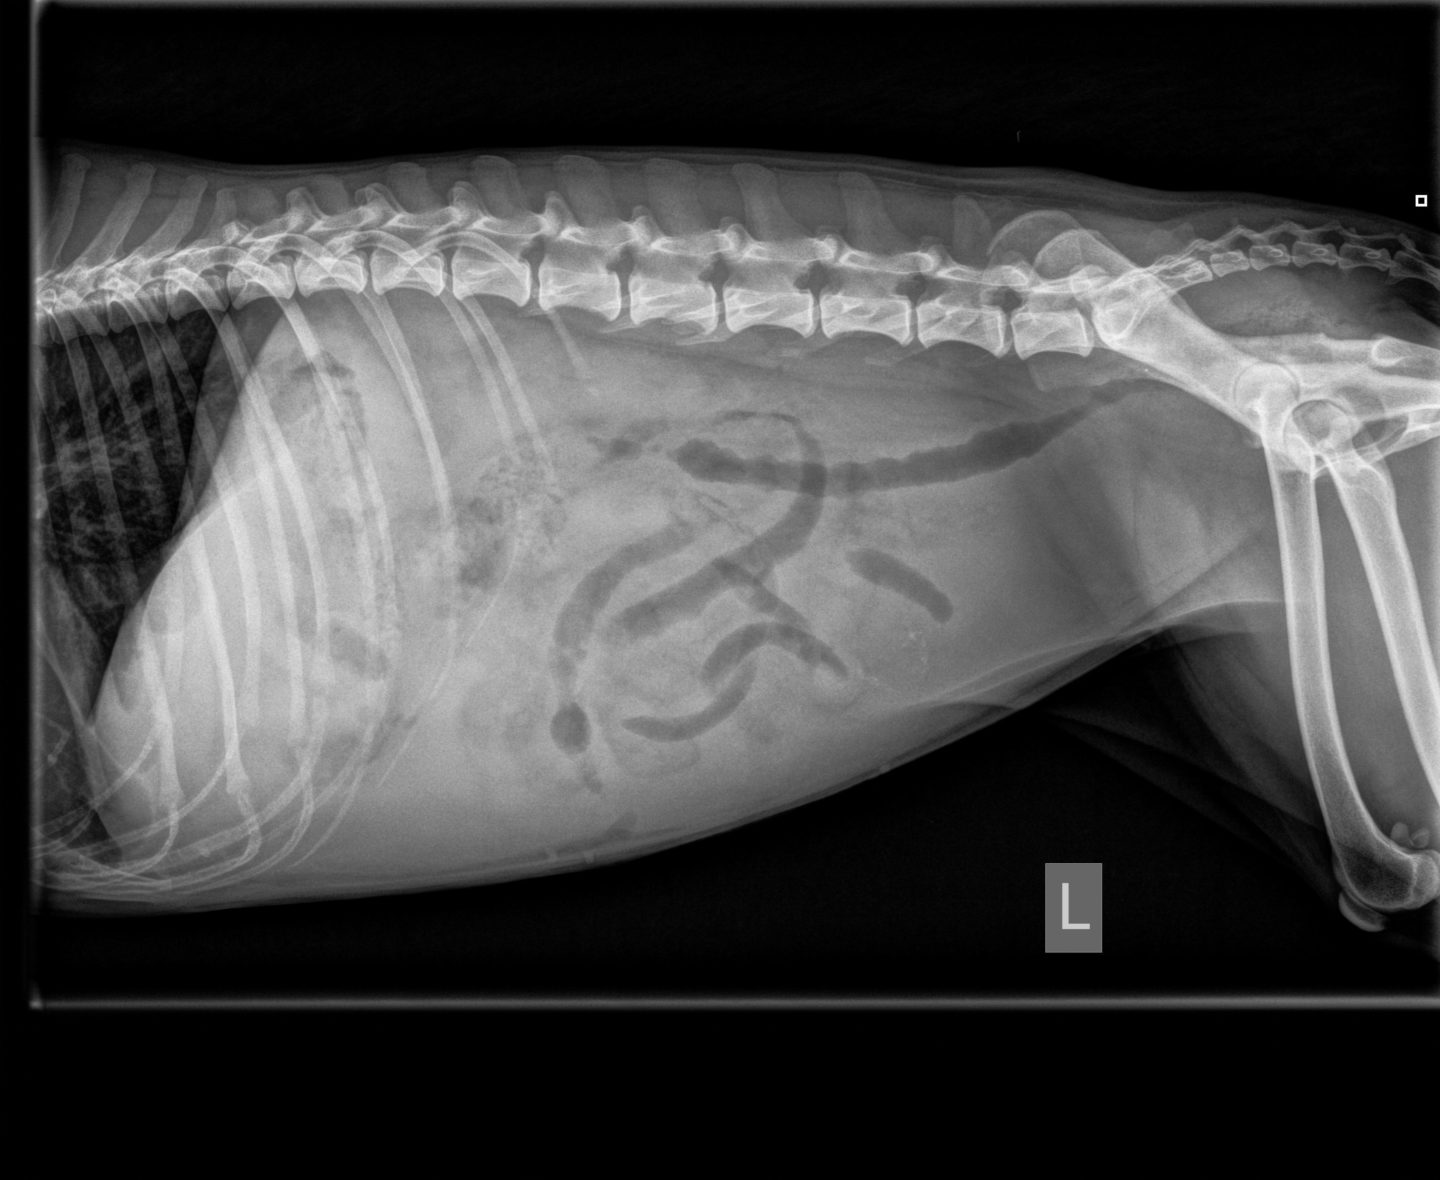

Auf den ersten Blick war weiterhin ein extrem praller Bauch zu sehen, die Schleimhäute im Maul waren trocken, pappig und grau-weiß, daher veranlasste ich sofort eine weitere Blutkontrolle. Die resultierenden Ergebnisse waren mehr als besorgniserregend, woraufhin eine Überweisung ins Tierspital geraten wurde. Da die Besitzer dies ablehnten, schlug ich eine Probelaparotomie (hierbei wird die Bauchhöhle eröffnet um mögliche Ursachen chirurgisch zu beheben, bzw. einen direkten Auslöser zu finden) an.

Bei der Probelaparotomie wurden anfänglichst ca. 2,5-3 Liter klare wässrige Flüssigkeit aus der Bauchhöhle abgepumpt. Abweichend wurde am Darm eine walnussgroße Umfangsvermehrung sichtbar, die Milz zeigte deutliche Auflagerungen mit weißen und gelben Herden von ca. 2mm Durchmesser und zudem noch eine deutlich verkleinerte puffige, mit Blasen komplett übersäte Leber. Aufgrund dieser Befunde, den dazugehörigen Blutwerten und dem Zustand des Hundes entschieden sich die Besitzer für eine Euthanasierung ihres Hundes, damit sie nicht weiter leiden musste.